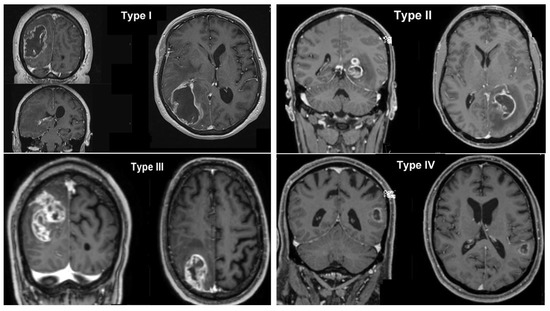

| Glioblastoma classification | |

| Type I | 100 (68) |

| Type II | 4 (2.7) |

| Type III | 41 (27.9) |

| Type IV | 2 (1.4) |